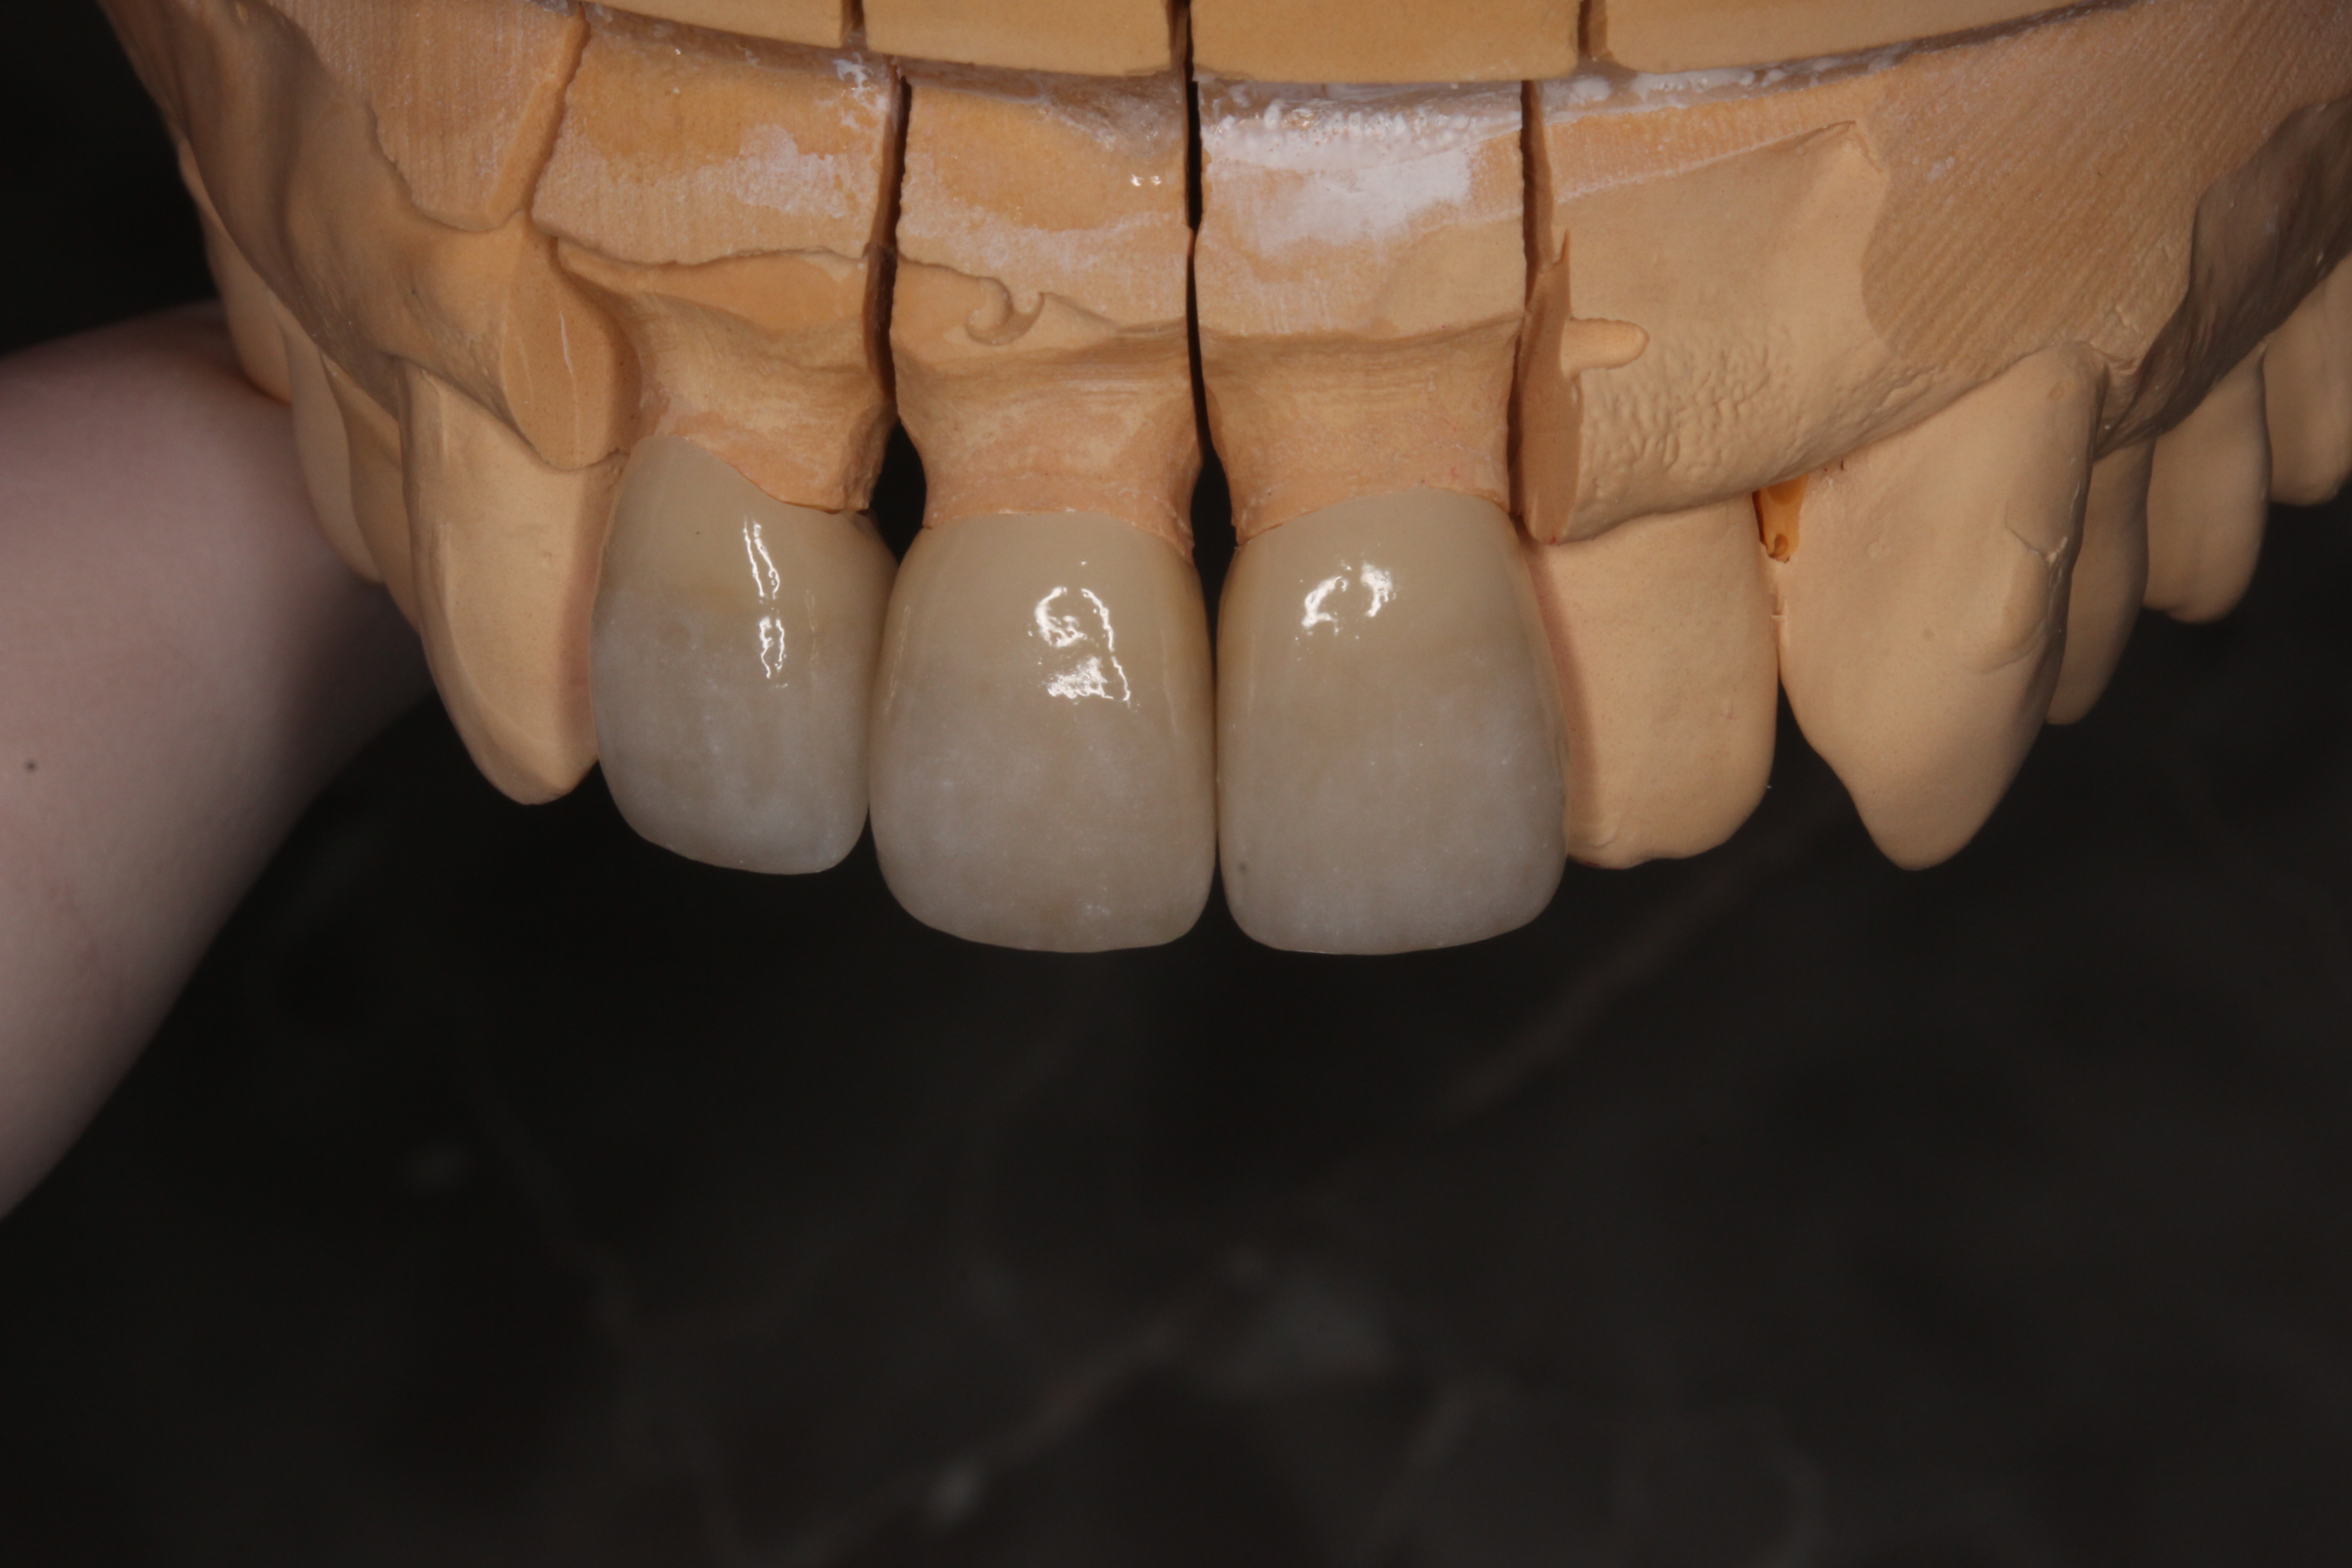

そして出来上がったセラミッククラウン。今度は1本ずつ単独です。

歯のグラデーションや色調を合わせ製作してもらいます。

ジルコニアセラミッククラウンといって、

ベースをジルコニアとよばれる材料(人工ダイヤモンド材料)

表面がセラミックで色調を合わせています。